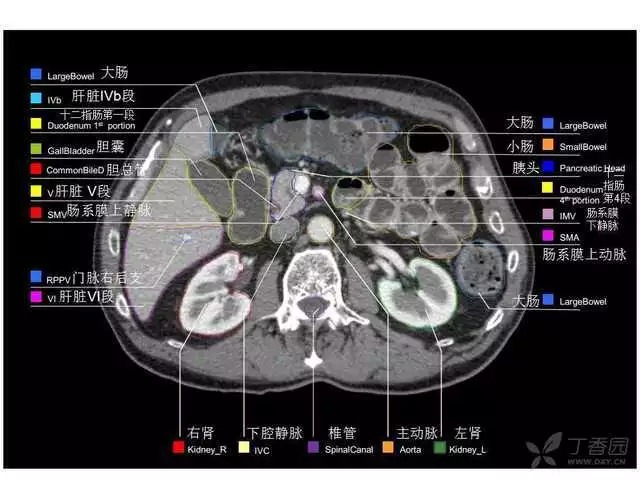

腹部肝脏高清CT断层的图谱

全腹部高清CT图谱,淋巴结彩色图谱,血管解剖图谱大汇总!

超声肝脏分叶及分段

肝脏分段和基本解剖学标志